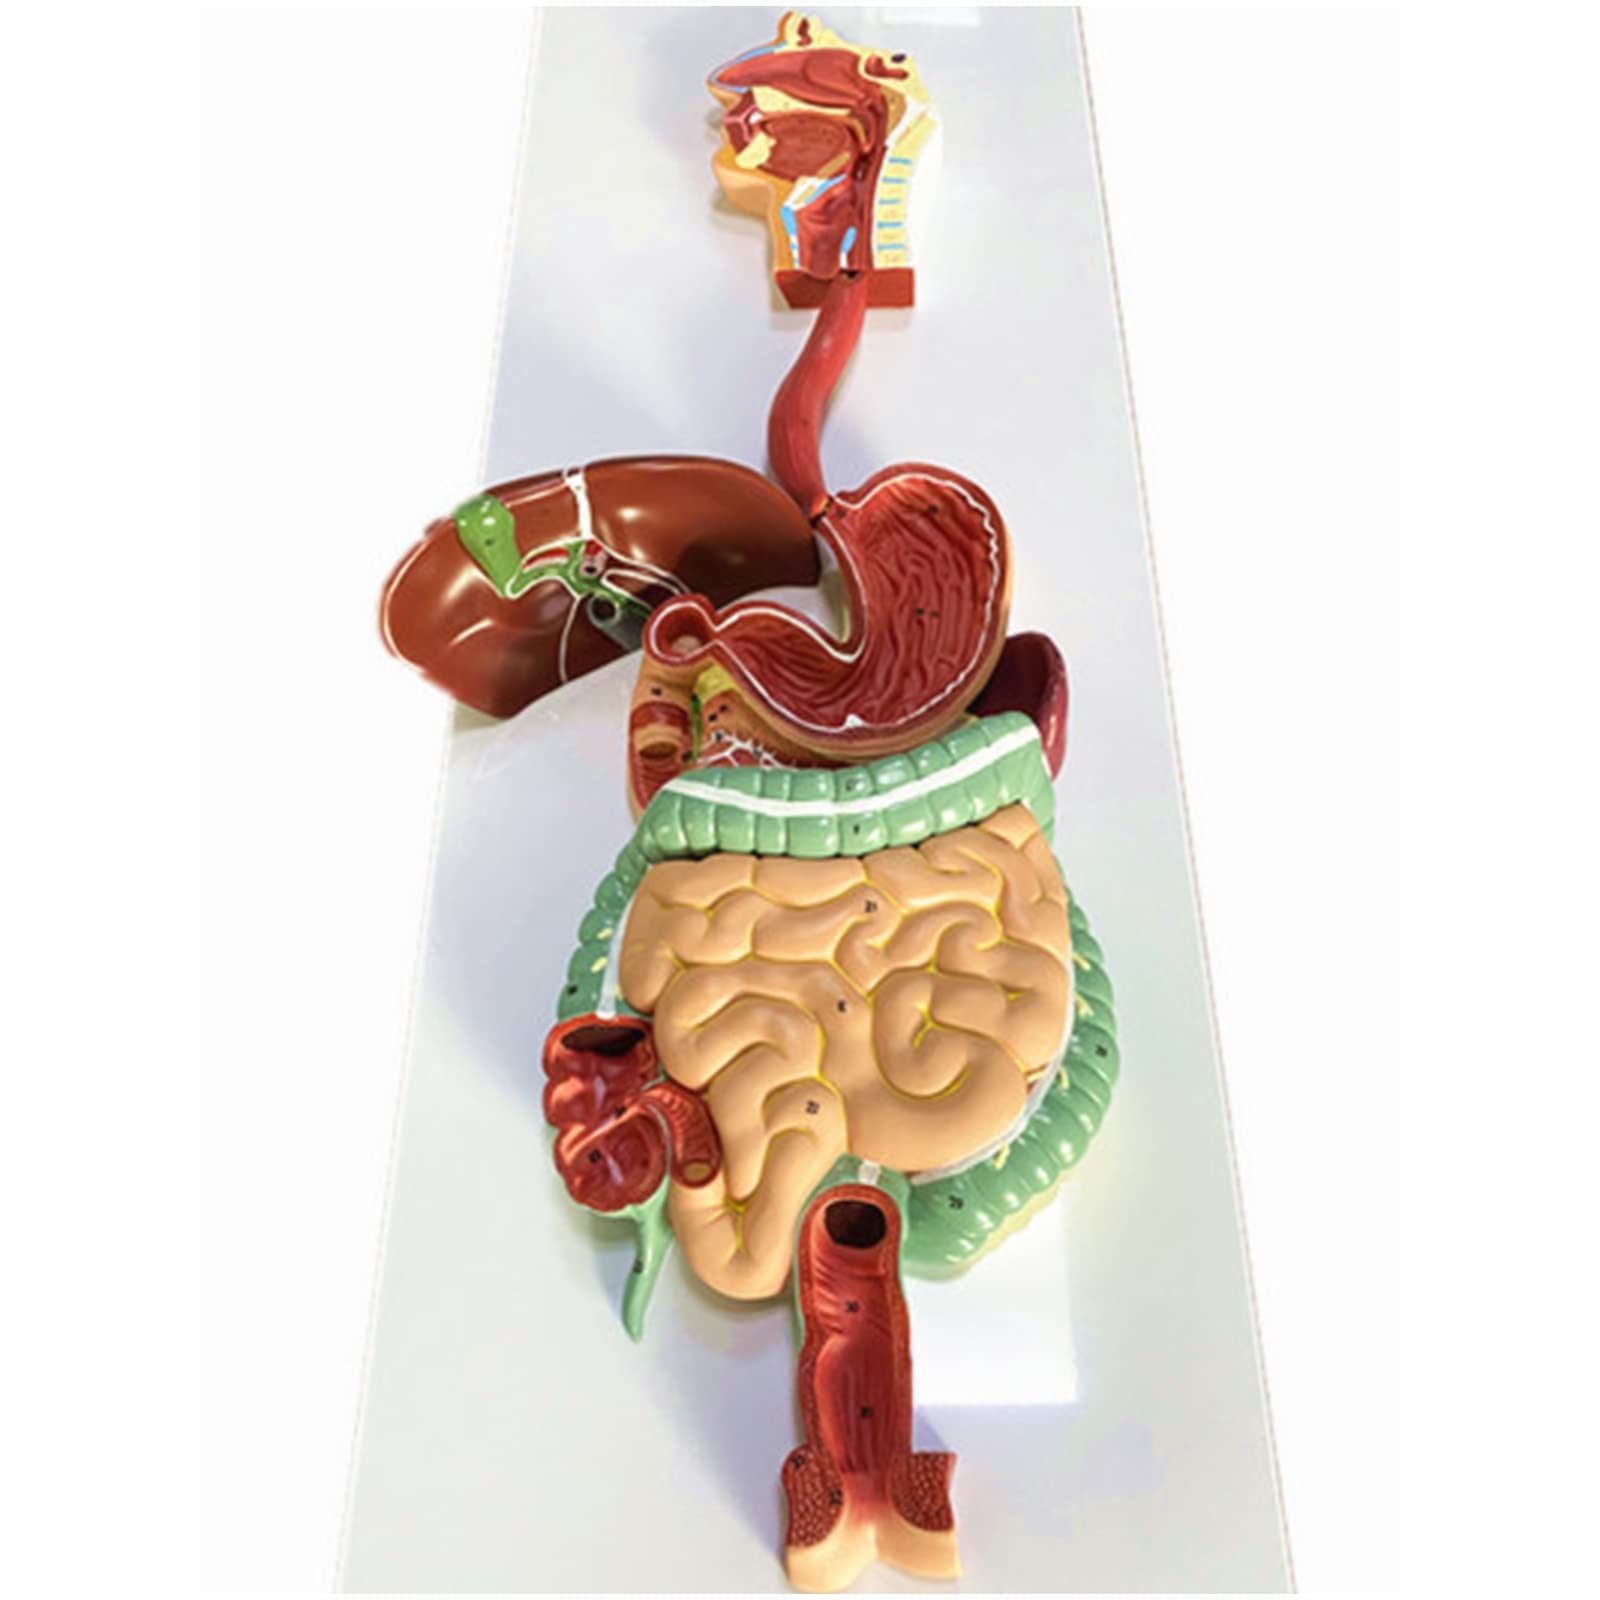

- INTERACTIVE LEARNING EXPERIENCE - Disassemble and explore the digestive system like never before!

The Human Digestive System Model is a life-size, three-dimensional representation of the human digestive tract, designed for educational purposes. It features disassemblable parts for interactive learning and is made from durable, anti-corrosive PVC material, making it an essential tool for anatomy students, educators, and healthcare professionals.